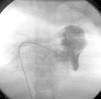

Caso 2Niño de 14 años, con antecedentes de ascitis y hepatoesplenomegalia. Ingresa por insuficiencia cardíaca con ascitis importante que requiere paracentesis evacuadora con extracción total de 10 l. En el ECG aparecían signos de crecimiento biauricular y sobrecarga del VD. Presentó varios episodios de fibrilación auricular y flutter con respuesta ventricular rápida. La cardiomegalia fue el hallazgo radiológico. En la analítica apareció una ligera eosinofilia. En el ecocardiograma se objetivó un VD de tamaño pequeño, con obliteración fibrótica del ápex, aurícula derecha aneurismática y afectación tricuspídea con insuficiencia severa (fig. 2). Las curvas de presión del VD del estudio hemodinámico mostraban morfología de tipo restrictiva, con aumento de las presión telediastólica y la angiografía del VD mostró obliteración del ápex (fig. 3). Recibió tratamiento médico, con mejoría clínica transitoria y a los 20 días reingresó por fallo cardíaco derecho. Ante la escasa respuesta al tratamiento médico, se decide realizar una intervención quirúrgica con decorticación del endocardio de VD afectado y anuloplastia de la válvula tricúspide. Durante los 3 años siguientes, ha precisado varios ingresos por insuficiencia cardíaca derecha e implante de marcapasos. Actualmente se encuentra en seguimiento ambulatorio por la unidad de insuficiencia cardíaca y trasplante.